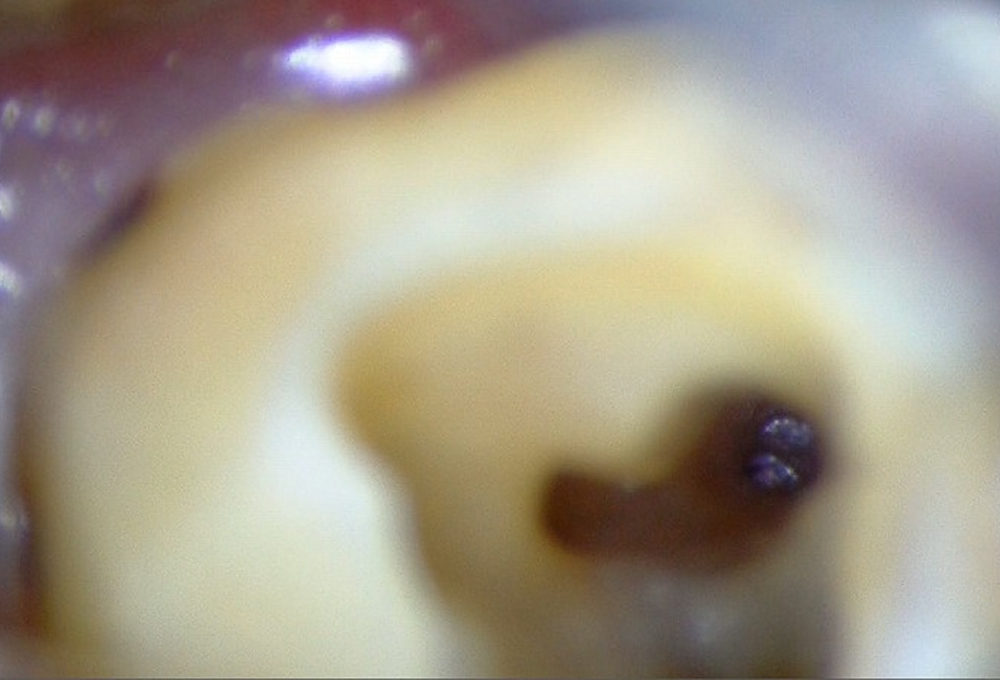

②マイクロスコープを使用して破折ファイル確認